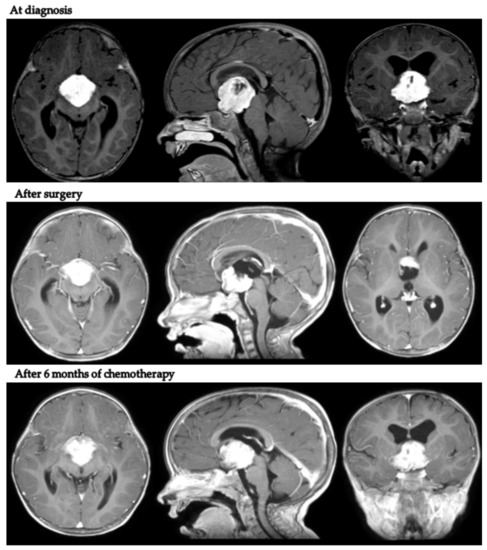

Intriguingly, in patient 9, despite tumor progression requiring a second surgical debulking after LGG 2004 standard induction treatment, the body weight continued to increase (+2.1 kg in 9 months). Figure 2 presents MRI scans of patient 9 at varying tumor stages.

Figure 2.

Axial, coronal and sagittal post-contrast T1-weighted MRIs of patient 9 at diagnosis, after neurosurgical biopsy and after the LGG 2004 induction protocol (1st progression).

MRIs at the end of first-line chemotherapy documented partial response in three cases and stable disease in five. Only one child (patient 9) progressed during first-line treatment, at the end of induction chemotherapy as per the LGG SIOP 2004 protocol (week 24).